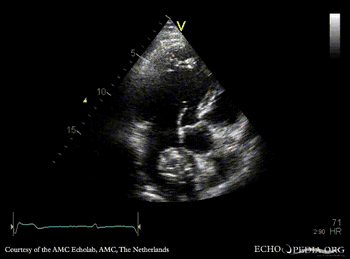

| PLAX: dilated left ventricle, myxoma in left atrium | PLAX: dimensions of myxoma |